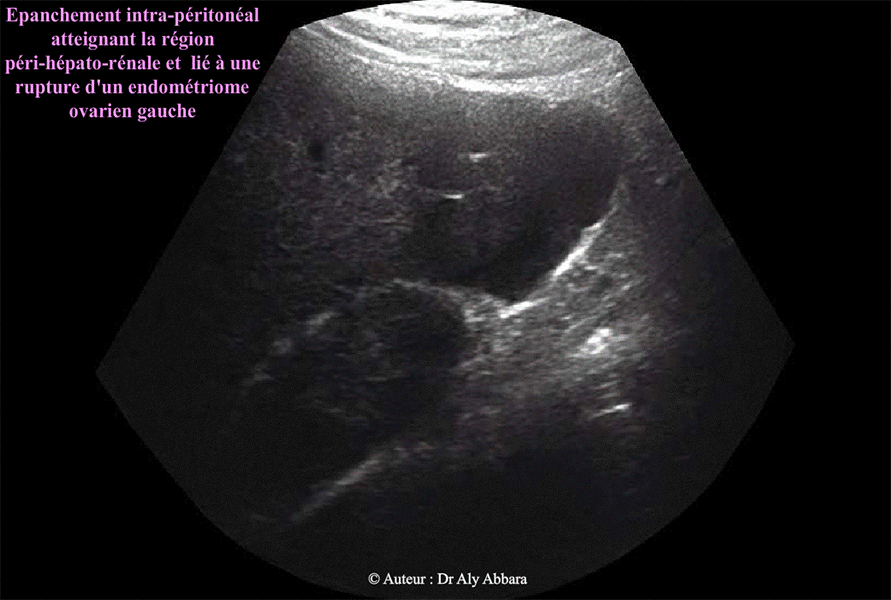

L'épanchement péritonéal

possède les mêmes caractéristiques échographiques du contenu de cet endométriome ; cliniquement, il s'agit d'une partie du contenu liquidien chocolaté qui a échappé du kyste suite à sa rupture spontanée.

Cet épanchement abondante

et diffuse dans l'ensemble de la cavité péritonéale, atteint la région péri-hépatorénale (espace de Morison).